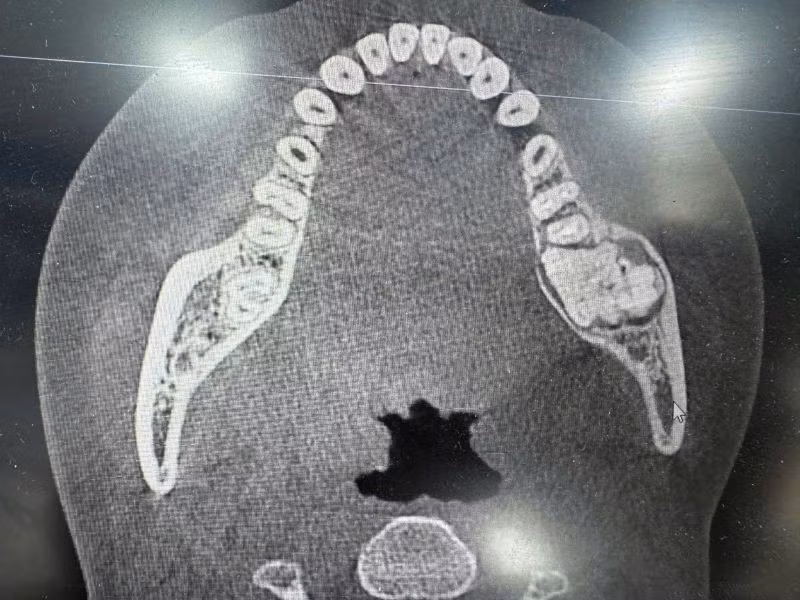

Khối u men răng trên phim chụp - Ảnh BVCC

u-men-xuong-1.jpg

Bệnh nhân N.T.N, 17 tuổi (Bình Thanh, Hưng Yên) đến Bệnh viện Đa khoa Kiến Xương (Hưng Yên) khám trong tình trạng sưng đau vùng mặt bên trái. Sau khi thăm khám và dựa vào các kết quả cận lâm sàng, bệnh nhân được chẩn đoán: U men xương hàm dưới trái và có chỉ định và tiến hành phẫu thuật ngay sau đó.

Các bác sĩ Bệnh viện Đa khoa Kiến Xương cho biết, u men xương hàm, hay còn gọi là Ameloblastoma, là một loại khối u lành tính thường gặp ở xương hàm, phát triển từ các tế bào tạo men răng.

Mặc dù là u lành nhưng nó có thể phát triển nhanh, phá hủy xương hàm và trong một số trường hợp hiếm, có thể chuyển thành ác tính. Bệnh có nguy cơ cao để lại di chứng nếu không được điều trị kịp thời, đặc biệt ở lứa tuổi còn đang phát triển.